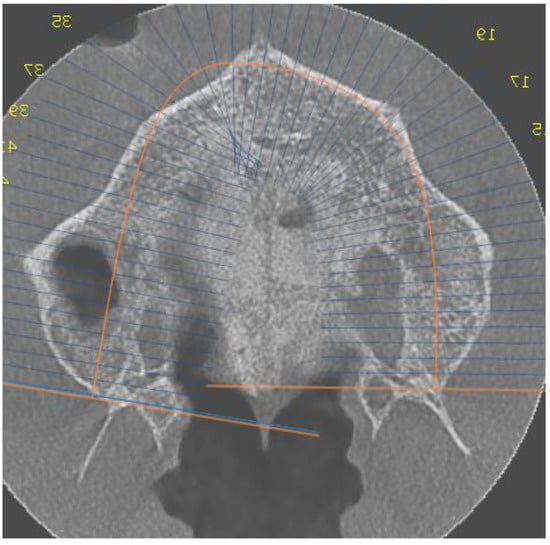

- Stage D or E palatal fusion (as seen in Angelieri et al. [18]) confirmed on CBCT prior to MARPE insertion;